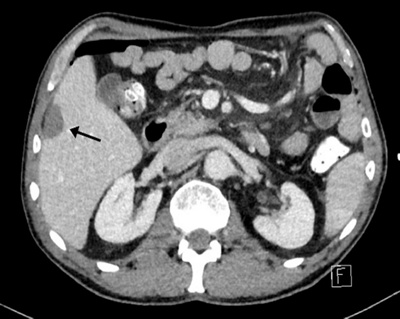

leber3

CT-Kontrolle 6 Monate nach der Ablation zeigt typische narbige Veränderungen (schwarzer Pfeil) ohne Anhalt für ein erneutes Tumorwachstum.